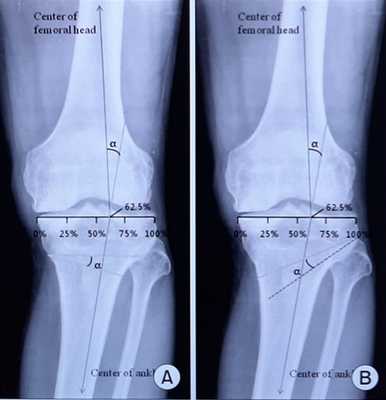

Учитывая высокую степень физической активности, наличие деформации, хорошо сохранный суставной хрящ в латеральных отделах коленного сустава принято решение о проведении высокой вальгизирующей остеотомии. При выполнении расчёта угла опила и степени раскрытия клина необходимо использовать либо полноразмерные снимки нижней конечности от тазобедренного до голеностопного сустава, либо МСКТ нижних конечностей с построением осей конечности.

![корригирующая остеотомия большеберцовой кости рассчёт угла]()

При выполнении коррекции желательно выполнять гиперкоррекцию, то есть переводить механическую ось в положение вальгуса 5-7 градусов, это увеличивает «выживаемость» процедуры и увеличивает время до конверсии к эндопротезированию.